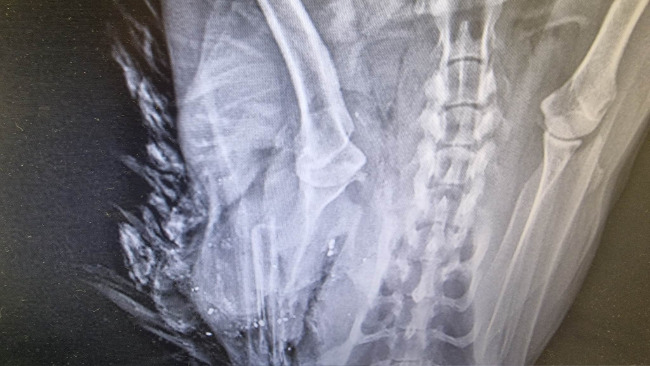

Rudek dostał ciężkiego obrzęku płuc. Rudek miał trochę gorsze płuca niż inni, bo miał je obite przy urazie, były trochę uszkodzone. Na zdjęciach była lekka odma opłucnowa. Cały się zalał, nie pomogły żadne moczopędne leki ani tlen. Umarł.